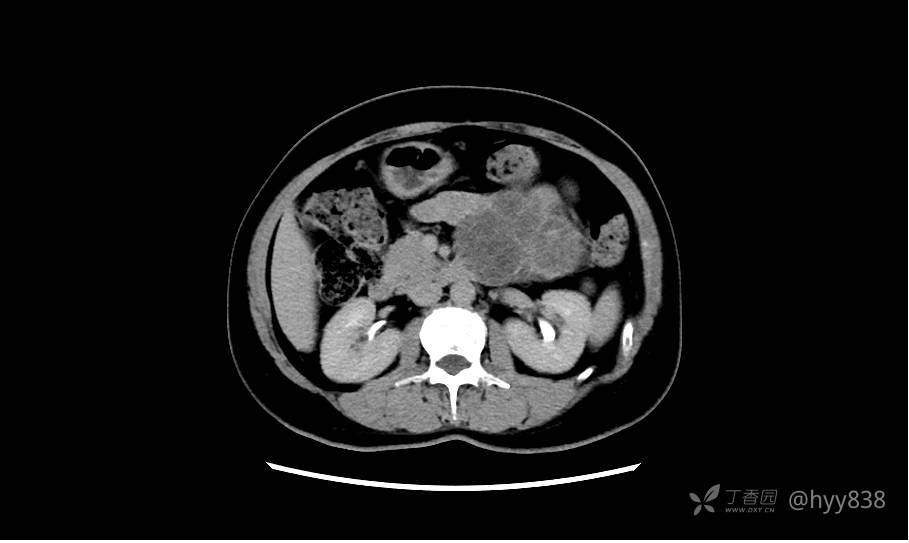

简要病史:2周前,患者无明显诱因出现剑突下不适,以隐痛为主,无明显加重、缓解因素。门诊以胰腺巨大占位收入院进一步诊治。

临床诊断:胰腺占位